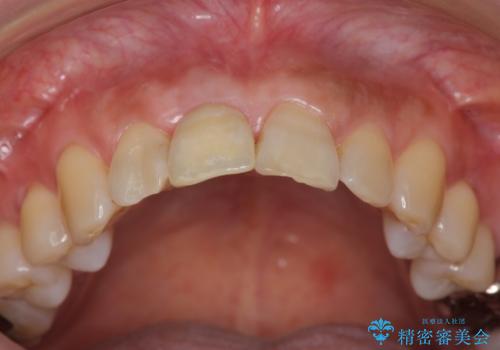

前歯のインプラントを審美的に仕上げるには、インプラント周囲に十分な骨の量と厚みのある歯肉、そして埋入位置の精密な位置付けが重要です。